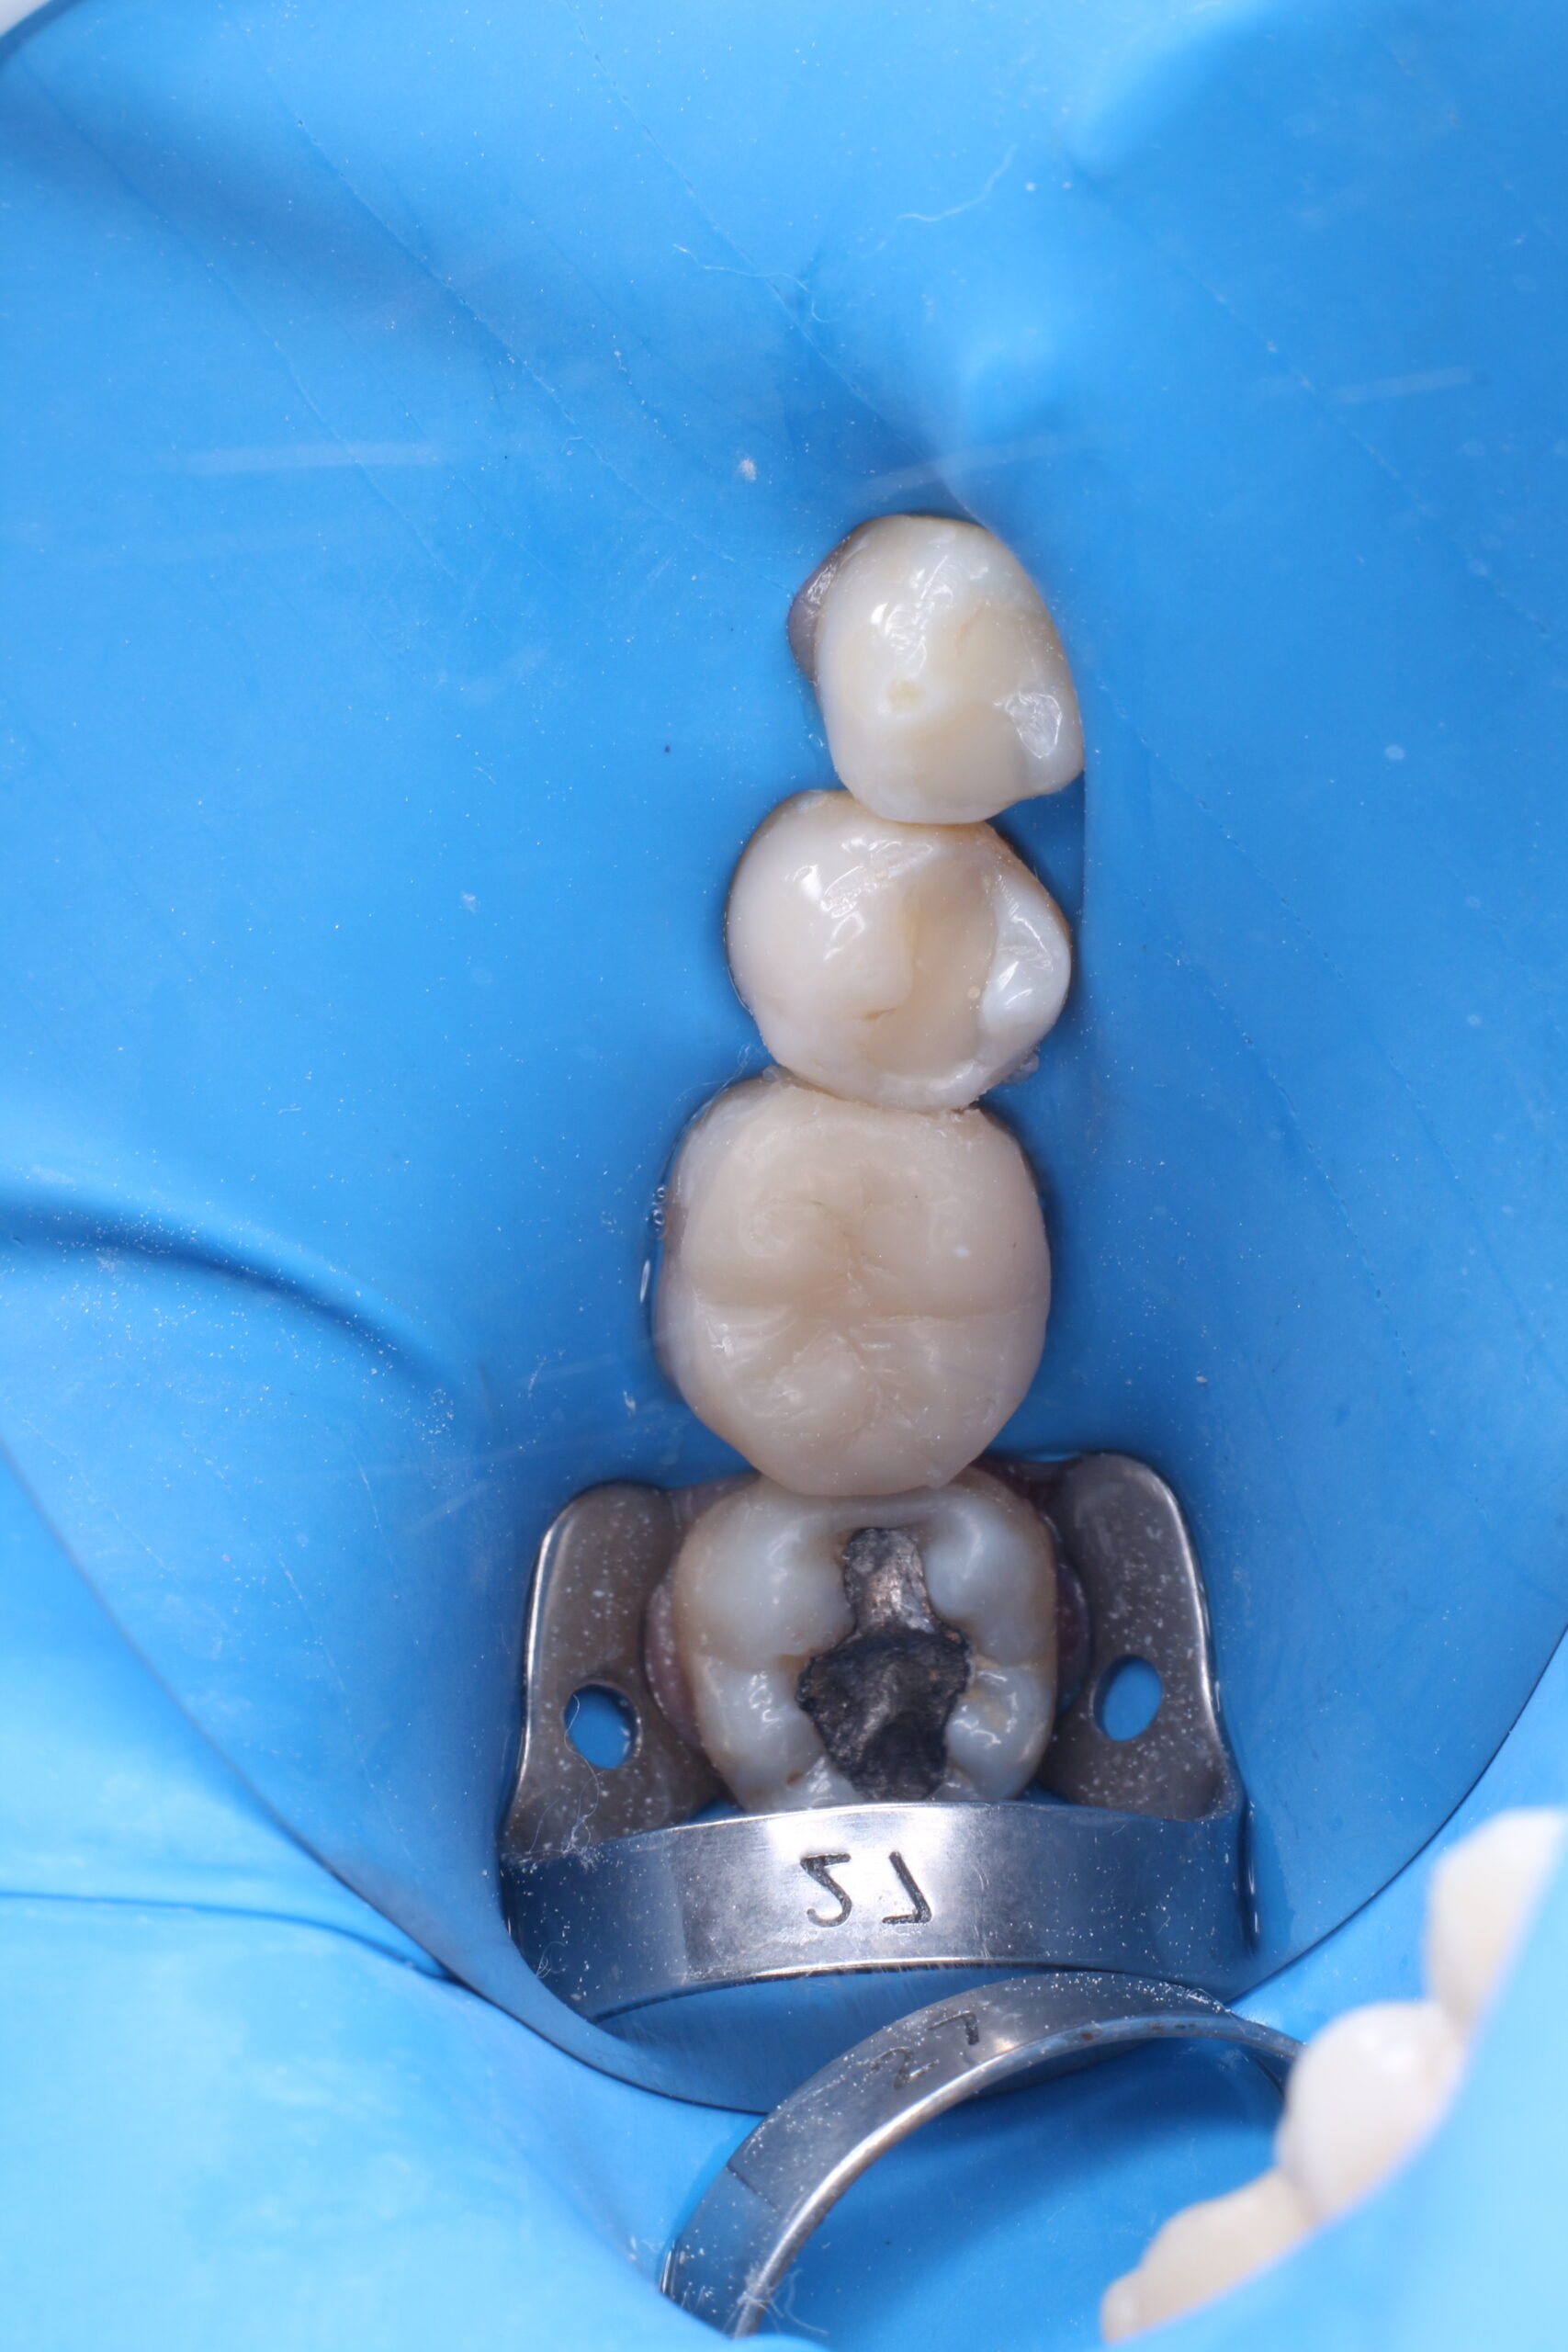

Incrustaciones

las incrustaciones son un tratamiento que conserva mucho tejido dental sano, sin llegar a necesitar desgastes excesivos, se indican en los molares en caries profundas y cavidades amplias despues de un tratamiento de conducto.

Nuestros molares tambien necesitan tratamientos sin desgaste excesivo

las cavidades que se forman en las muelas y destruyen gran parte de la misma, pueden ser rehabilitadas con un tratamiento conservador, con ayuda de laboratorios dentales, se confecciona una restauracion que ayuda que la muela no se fracture en poco tiempo

Incrustaciones De Resina o Cerámica desde $150